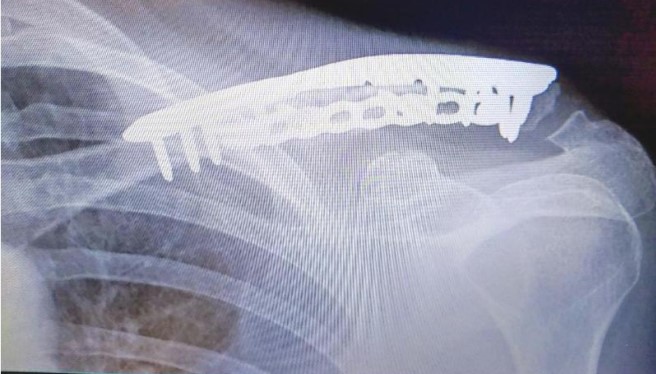

Following a major car accident in February 2024 that left me with multiple injuries, Dr. Sama led me through a challenging recovery that included several complex surgeries, the last of which took place in December 2025.